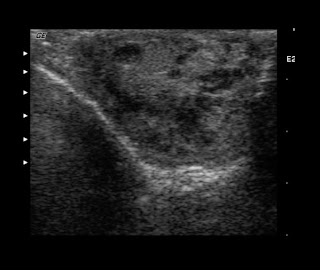

Sonogram depicting a combination of an intratesticular and extratesticular right-sided varicocele.